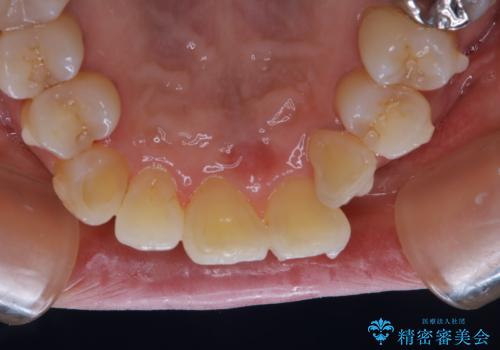

インビザラインの治療中の患者様のクリーニング前後写真です。

- インビザラインの矯正治療中に歯石や着色(ステイン)が付着してしまっていたため、歯科衛生士による専門的クリーニングを行いました。

今回はお口全体に歯石や着色(ステイン)が付着していたため、自費のPMTC(クリーニング)60分コースをご案内し、徹底的に除去しました。